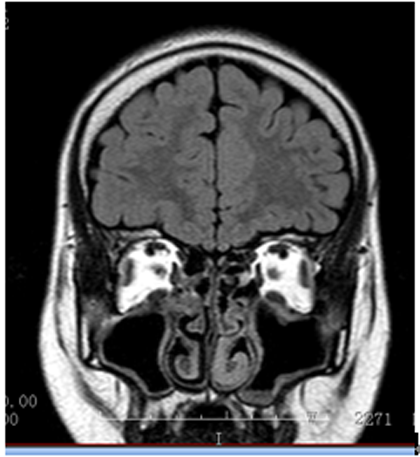

入院诊断:癫痫。入院后完善相关检查,VEEG:发作期:眨眼→左侧面肌、上肢强直→左侧偏转→BAST(左)→GTCS。MRI:右侧眶额回灰白质分界不清,弥漫性脑萎缩。PET:右侧额极及内侧面低代谢,右侧眶额回稍低代谢,右侧岛叶代谢减低。韦氏智力:全量表83,言语78,操作91;记忆63。染色体结果:47,XXY。

▲ 2T2FLAIR冠状位